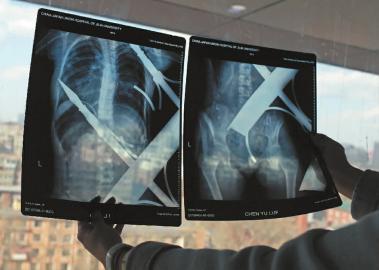

X光片顯示一根鋼筋將小女孩的右側(cè)肩膀刺穿,另外一根則從后背腰部以上靠近脊椎的地方穿入 白石 攝

在急診室的病床上,李紅旭看到了小雨?!八龗熘跗?,意識比較清醒?!边M一步觀察,李紅旭一時說不出話來———一根鋼筋穿透小雨右側(cè)肩膀,另一根則從后背腰部以上靠近脊椎的地方穿入,從小雨左肩部分穿了出來。兩根鋼筋由兩根角鐵連接,距離事發(fā),小雨背著這片鐵柵欄已經(jīng)近7個小時了。